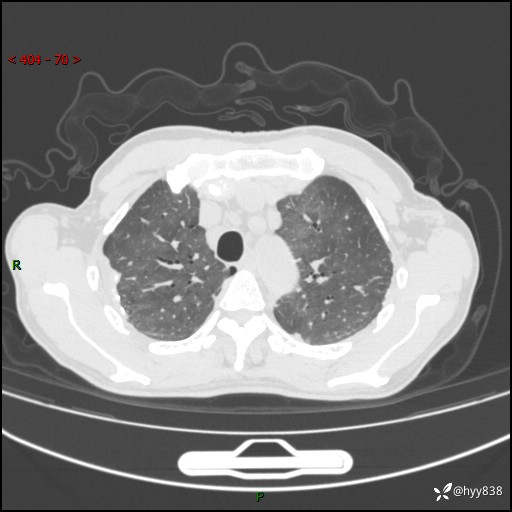

辅助检查:CT

胸部CT平扫

不是讨论肺部结节